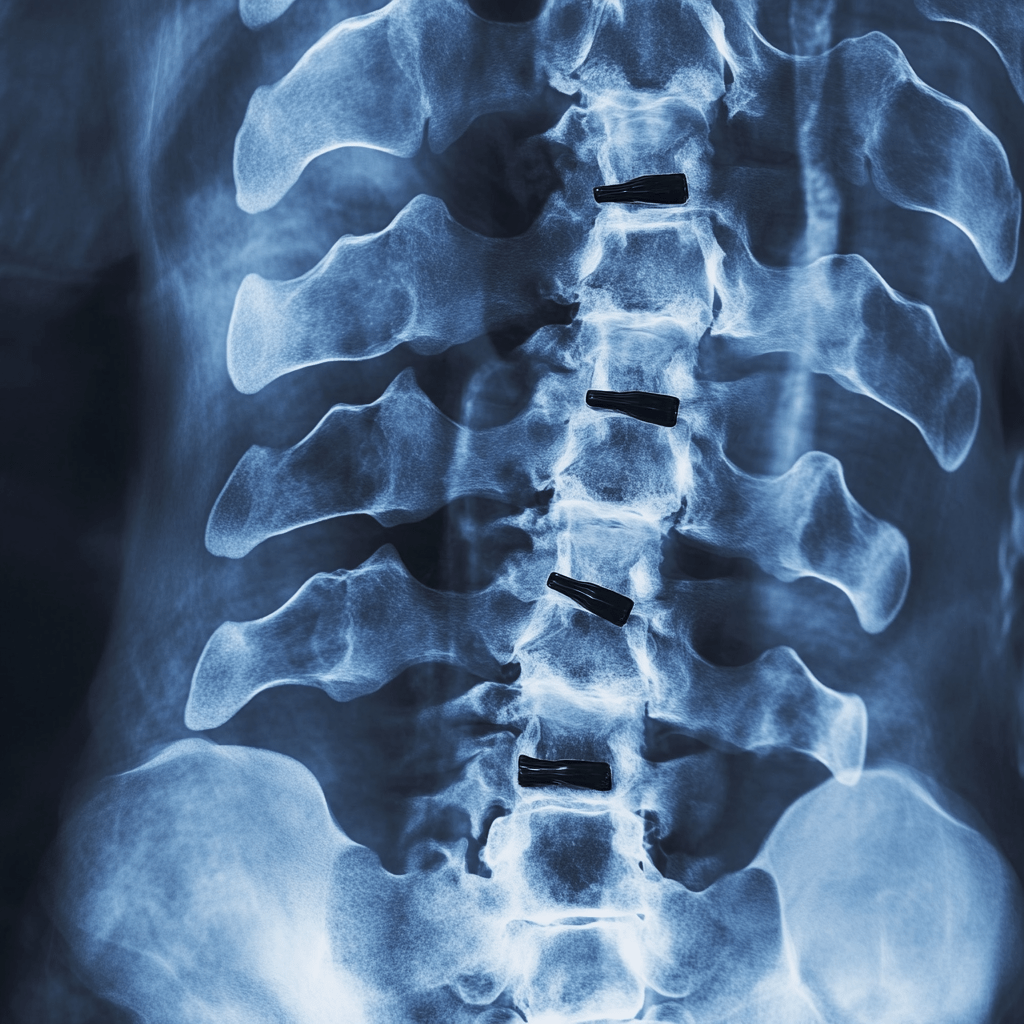

Tratamientos Avanzados para la Columna Vertebral

El dolor crónico de columna es la principal causa de incapacidad en el país.

Este padecimiento requiere de un tratamiento específico y adecuado para cada caso.